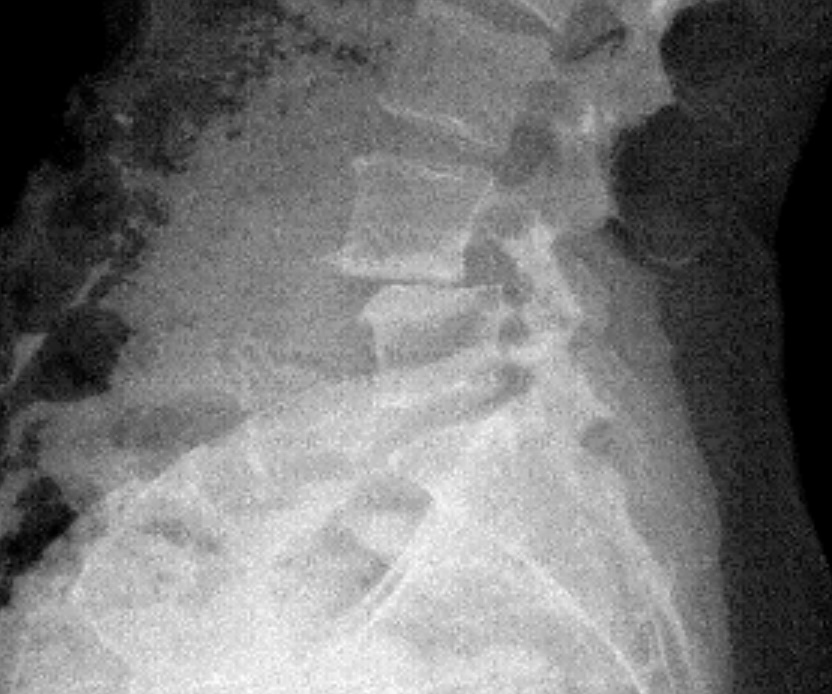

I’ve always been active. I’ve done everything - boxing, Pilates, barre, and in my mid-40s after Covid I started to run and ran two half marathons in 2022 and 2023. I first started to experience pain in my hip and down my right leg during my first pregnancy. The leg pain subsided but the hip pain never did. When I took up running, that’s when things went downhill. First the plantar fasciitis, then the constant leg pain like I had pulled a hamstring. Dr. Baxi at first used cortisone on both my foot and back. Then we did shockwave therapy on my foot which helped tremendously. But after a second epidural on my back didn’t work I knew it was time for surgery. Dr. Dowdell was great. It was tough at first and he assured me after six months I could get back to my former life. Now I’m back to boxing and I’m hoping to start training for and run in the NYC marathon this Fall.

James E. Dowdell III, MD

Spine Surgeon